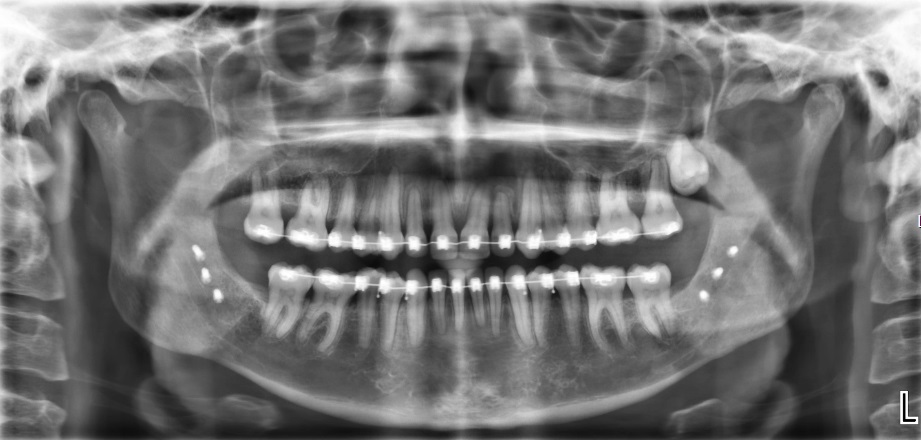

Röntgen beeld na operatie